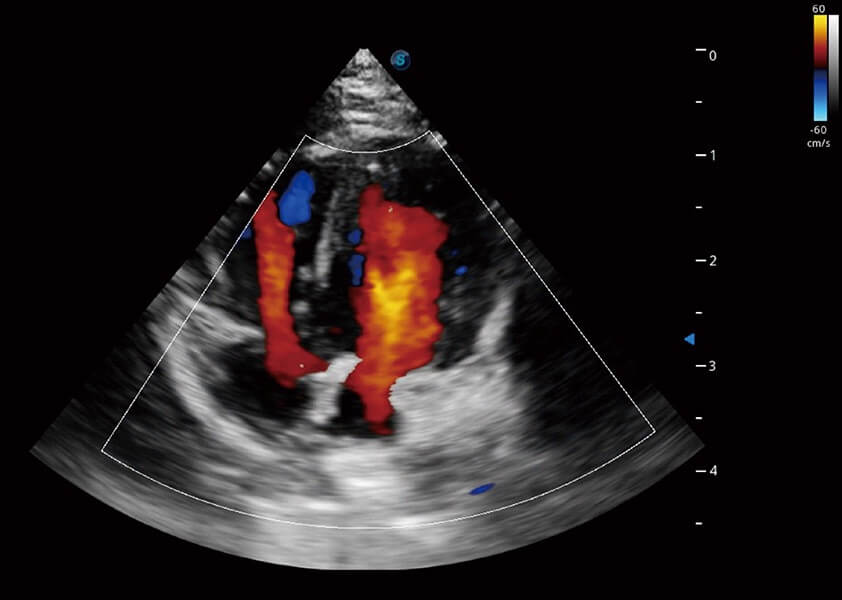

ProPet 60 作为一款高端台式动物超声设备,为动物医生的日常诊断提供了一系列贴合动物临床需求、解决临床实际问题的高级成像功能。凭借全系列高清探头,满足医生对腹部、心脏、生殖、浅表、肌骨等成像的所有需求,切实帮助您提升检查效率,提高诊断信心。

兽用彩色多普勒超声诊断系统